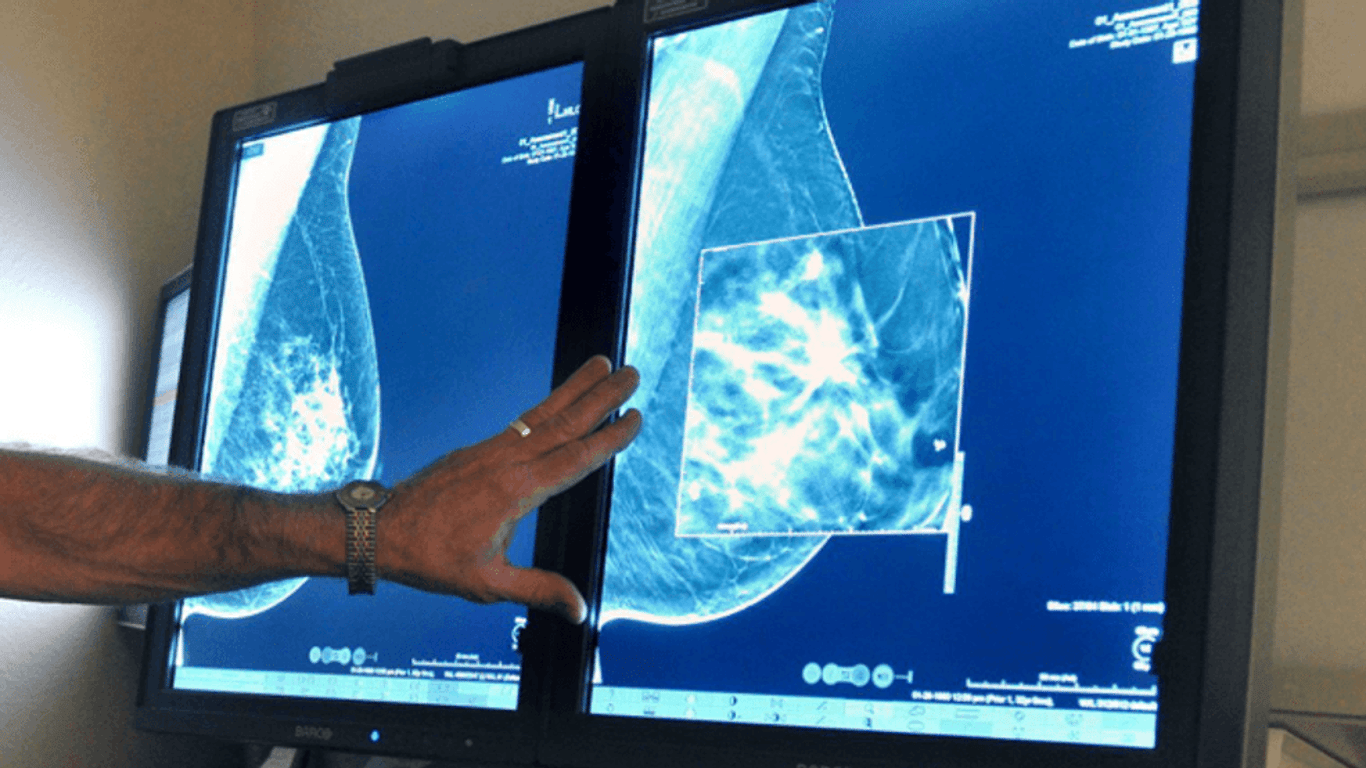

Las mujeres de toda América están recibiendo información importante que podría impactar significativamente su salud, ya que las recientes regulaciones federales exigen que los informes de mamografías incluyan detalles sobre la densidad mamaria. Este desarrollo es crucial, ya que el tejido mamario denso, que afecta a más del 40% de las mujeres, puede ocultar tumores durante las mamografías estándar, lo que retrasa diagnósticos críticos de cáncer. Sin embargo, el desafío va más allá de la simple conciencia; el Congreso está intensificando sus esfuerzos para asegurar que las mujeres tengan acceso a las pruebas de seguimiento necesarias.

El tejido mamario denso plantea una complicación única en el diagnóstico del cáncer de mama. Debido a que tanto el tejido denso como los tumores aparecen en blanco en las mamografías, estos últimos pueden volverse difíciles, si no imposibles, de detectar. Para muchas mujeres, esto se ha traducido en diagnósticos en etapas avanzadas, con consecuencias devastadoras. La Dra. Noelle Cutter, profesora asociada en la Universidad Molloy, ha estado investigando este problema durante varios años. Su indagación fue impulsada por el creciente número de diagnósticos de cáncer de mama entre sus amigas, mujeres que son sanas y en forma, pero que aún enfrentan las duras realidades del tratamiento del cáncer.